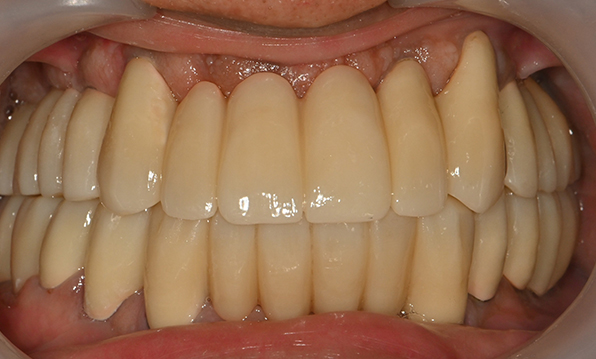

Before & After

| Before | After |